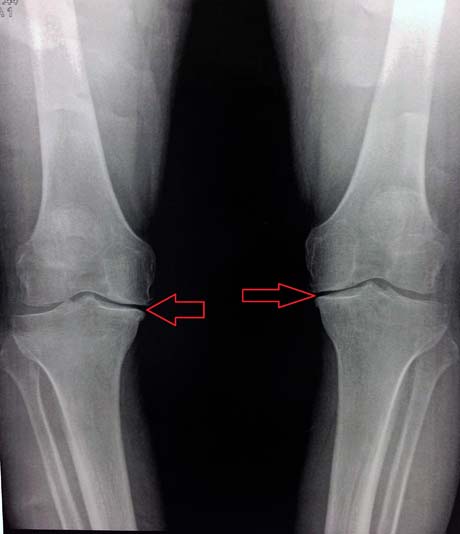

Άντρας 48 ετών με έντονη παραμόρφωση των γονάτων σε ραιβότητας ιδίως το δεξί κάτω άκρο. Ο μηχανικός άξονας του άκρου έχει επηρεαστεί σοβαρά δημιουργώντας έναν φαύλο κύκλο επιφόρτισης της εσωτερικής πλευράς του γόνατος (έσω διαμέρισμα) και εμφάνιση πρόωρης εκφυλιστικής οστεοαρθρίτιδας σε νεαρή σχετικά ηλικία.

Ο ακτινολογικός έλεγχος των γονάτων αναδεικνύει το πρόβλημα της αρθρίτιδας στο έσω διαμέρισμα του γόνατος. Η αξιολόγηση του μηχανικού άξονα των κάτω άκρων θεωρείται απαραίτητη.

Αρθρίτιδα στο έσω διαμέρισμα των γονάτων (βέλη)